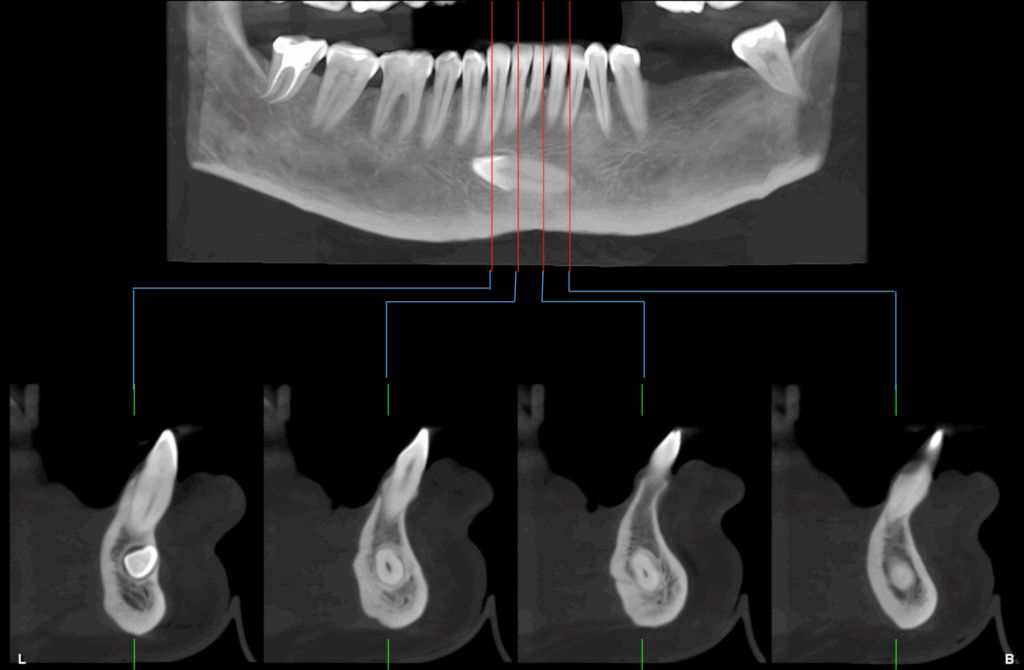

A la evaluación de la tomografía cone beam de campo mediano se puede observar que dicha pieza se encuentra caudal al ápice de las piezas 32, 31, 41, 42 y 43 con la porción coronaria en contacto y adelgazando la tabla ósea vestibular y la porción radicular se encuentra equidistante a ambas tablas óseas y la presencia de un foramen lingual. Se descartar cualquier relación con piezas dentarias vecinas

CORTES TRANSAXIALES

CORTES TANGENCIALES